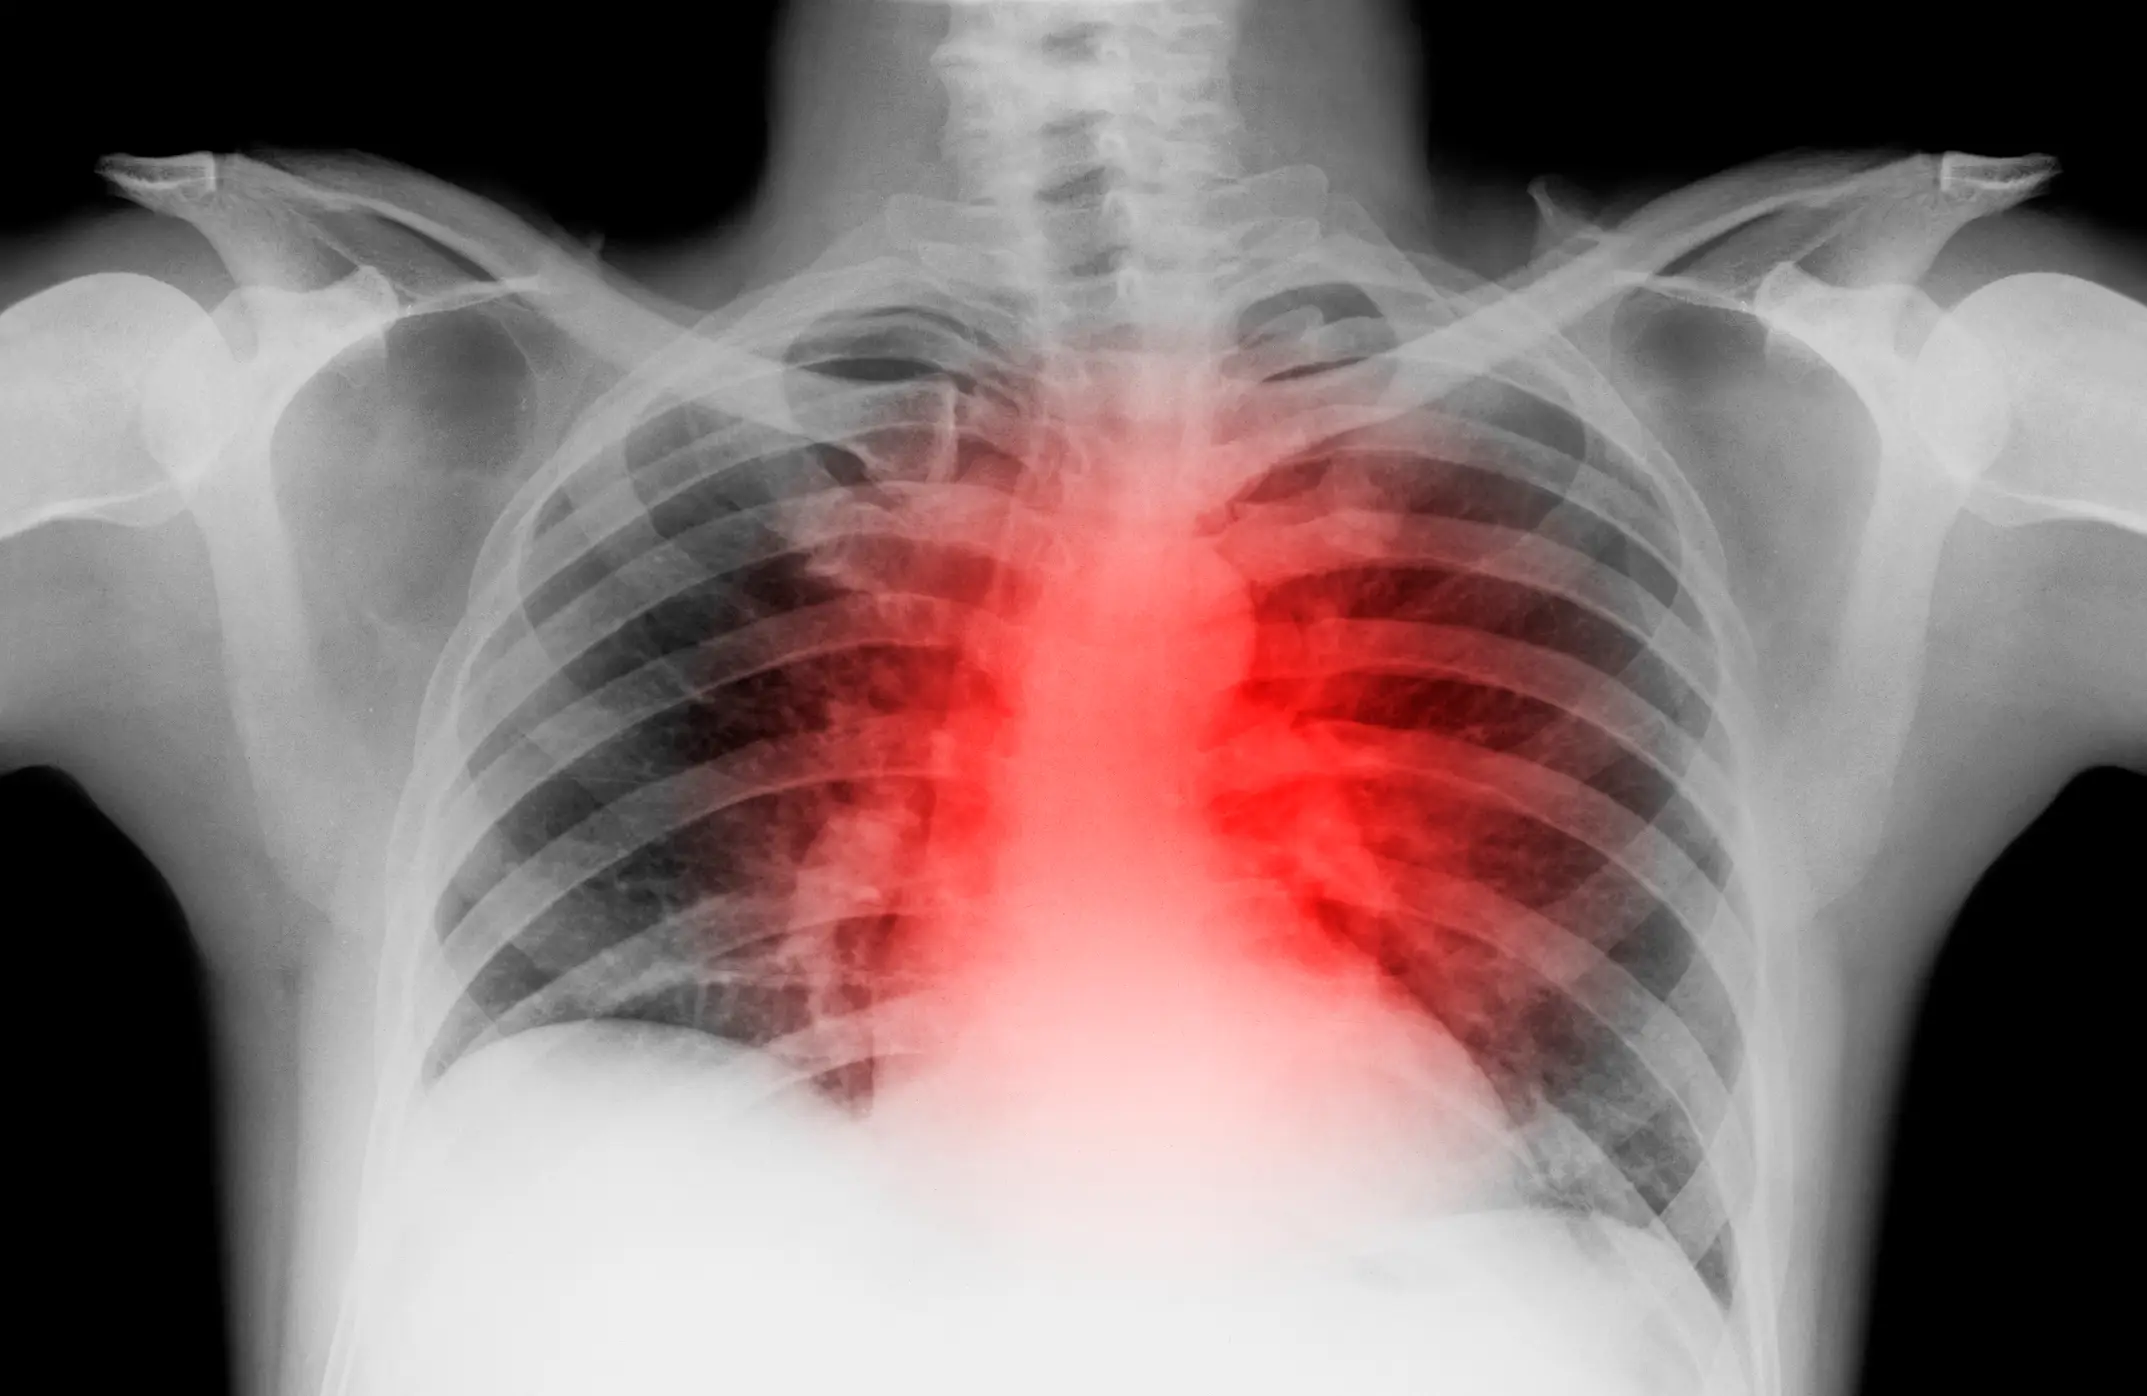

The symptom, which is similar to that of a heart attack, occurs when there is inflammation at the point your ribs join the bone in the middle of your chest (breastbone).

Costochondritis, as the condition is called, usually causes a sharp pain in the centre of the chest.

This may worsen when you move your upper body, lie down, breathe deeply, or press the middle of your chest.